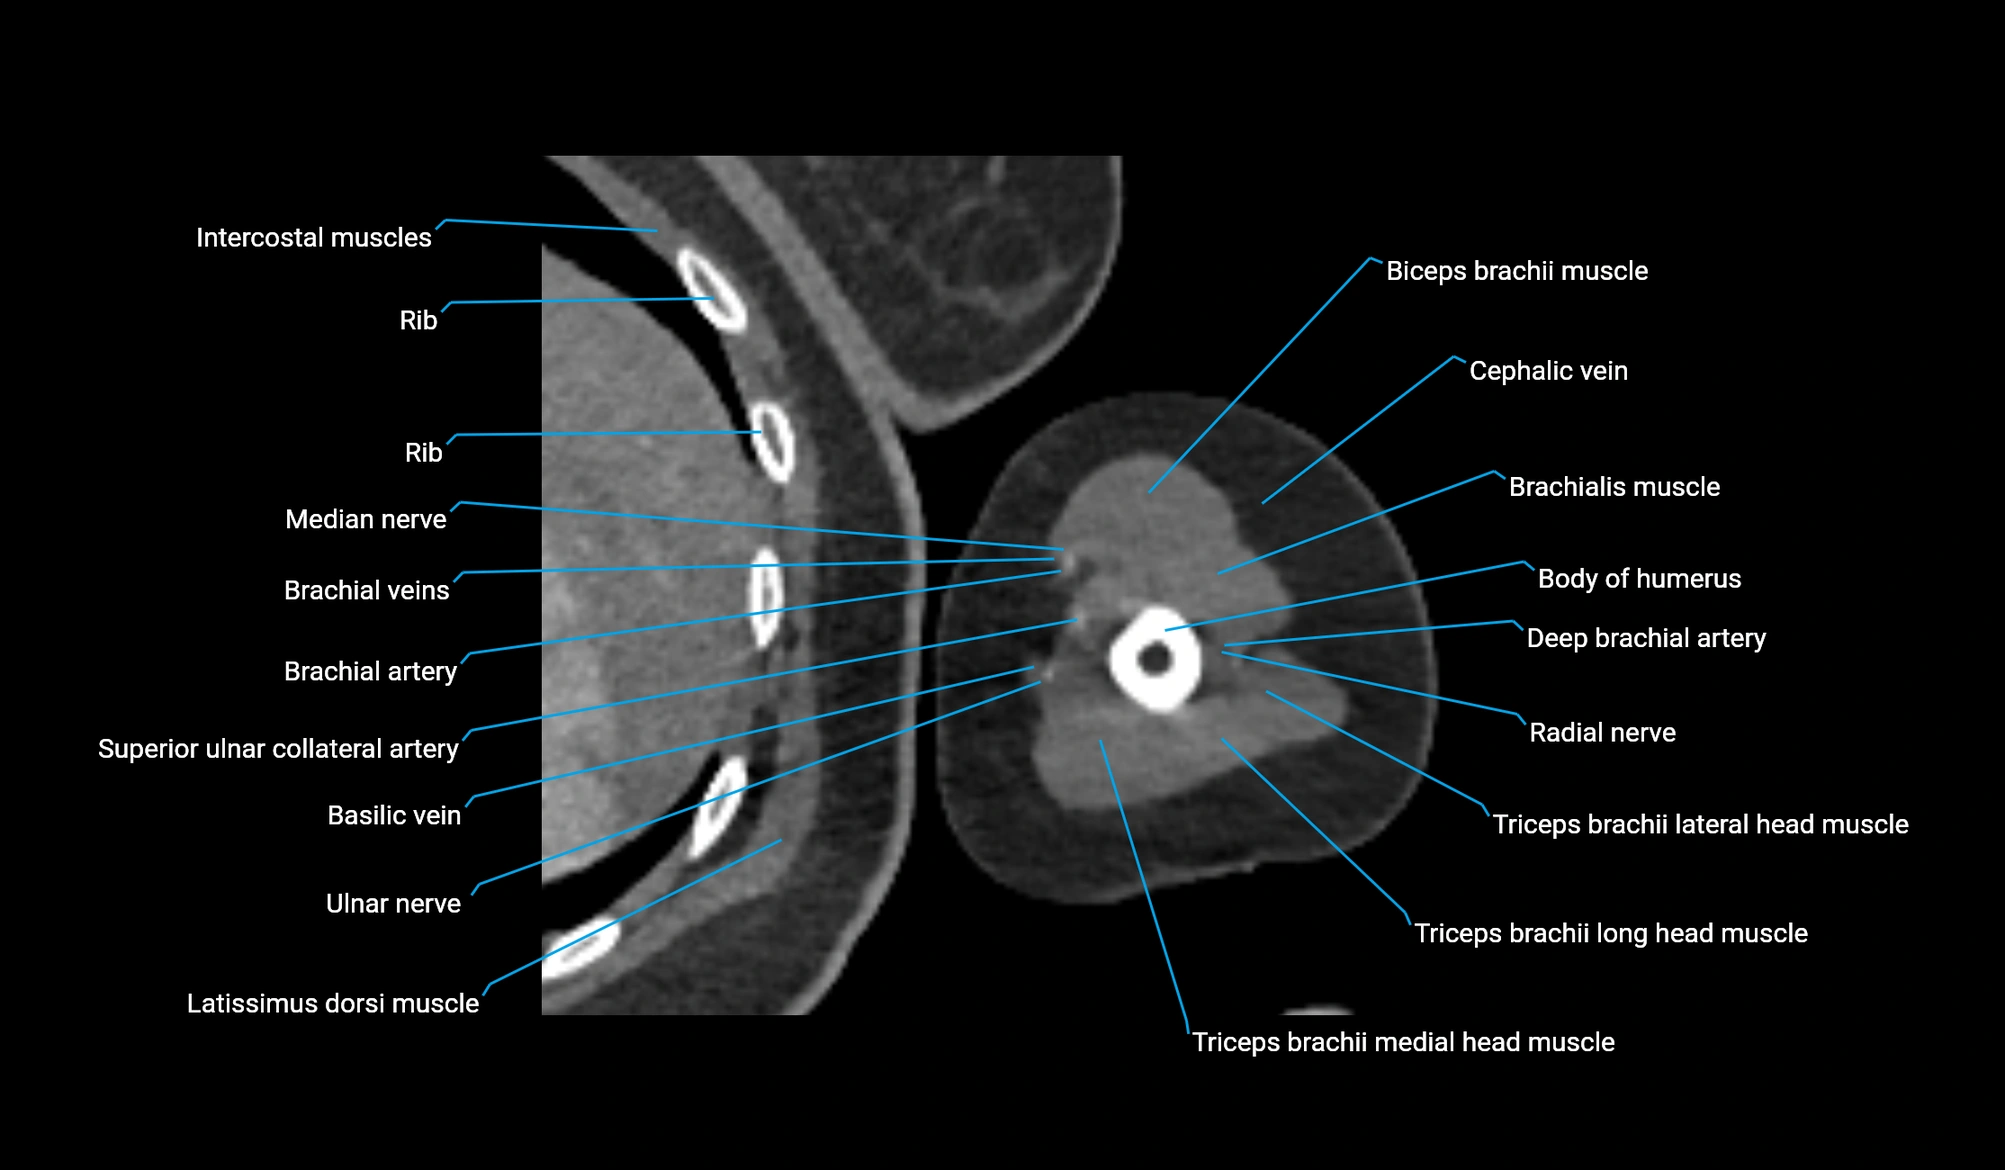

- Body of humerus

- Brachial artery

- Brachialis muscle

- Brachioradialis muscle

- Cephalic vein

- Deep brachial artery

- Long head of triceps brachii muscle

- Lateral head of triceps brachii muscle

- Medial head of triceps brachii muscle

- Biceps brachii muscle